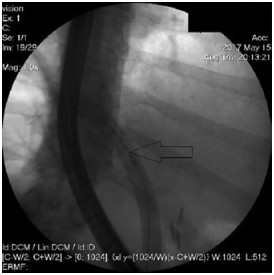

Abstract: Hilar cholangiocellular carcinoma (CCC) is a malignant neoplasm of epithelial origin occurring at the confluence of the right and left hepatic bile ducts. Typically, these tumors are small, poorly differentiated, exhibit aggressive biologic behavior with non-specific symptoms and tend to obstruct the intrahepatic bile ducts. Surgery is the only available curative option. Unfortunately, in less than half of the patients a complete resection is possible with poor survival rate in unresectable cases. In this report, we present the case of a 58-year-old woman with a history of unresectable hilar cholangiocarcinoma. Initially she was treated with intraductal dilatation of malignancy and placement of a plastic stent and chemotherapy (Gemcitabin® and Platinol®). Two years later she underwent a second-line chemotherapy with Gemcitabin® and Oxyplatin® because of tumor progression. Despite a second line chemotherapy and placement of an uncovered self-expandible metal stent (ucSEMS) that was extended later on by stent-in stent technique, there was tumor progression which led to a complex course with relapsing obstructive cholangiosepsis and cholestasis. Because of tumor ingrowth, endobiliary radiofrequency ablation of the malignant stenosis was performed in repeated sessions. This case illustrates that radiofrequency ablation of solitary malignant biliary obstruction is feasible, safe and allows an improvement of quality of life in non-operable patients.